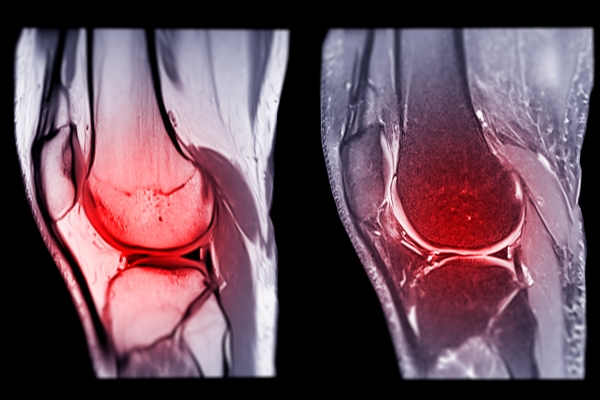

Well first, I would really like to point out that ACL tears occur at all levels of sport and it can be one of the worst injuries an athlete can suffer. The Anterior Cruciate Ligament or commonly known as the ACL is a major ligament that really helps to stabilize the knee. Without getting too technical, it attaches the femur bone (upper leg) to the tibia bone (lower leg/shin) and runs across and through the main joint of the knee. Its main purpose is to keep the tibia bone from moving forward.